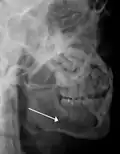

- lateral oblique image demonstrating a fractured mandible.

- Towne's view of a bilateral condyle fracture. White arrow is a fracture on the neck of the condyle. Black arrow shows the condyle pulled to the medial. The same injury can be seen on the opposite side